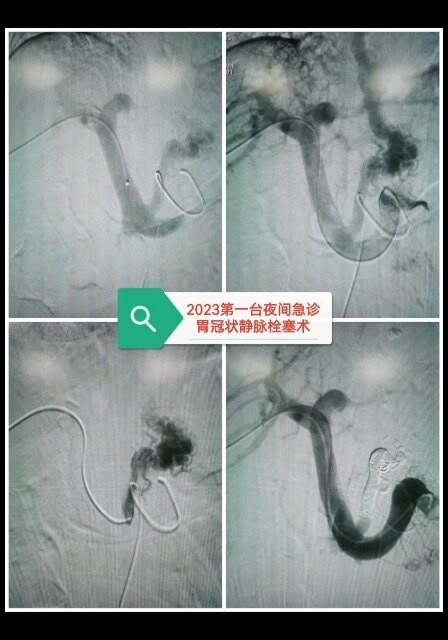

“奇跡!七天不吃餓死癌細(xì)胞!”“震驚!一個(gè)癌癥患者吃素痊愈的故事!”癌細(xì)胞真的能被餓死嗎?事實(shí)并不是想象中那么簡(jiǎn)單,前華為高管魏延政在患癌后使用了多種治療方法,他甚至嘗試了斷食療法,進(jìn)行了多次長(zhǎng)達(dá)20到24天的斷食,期間只喝礦泉水和藥物,不進(jìn)食任何食物,為了餓死癌細(xì)胞,在生命的最后半年,魏延政嘗試過(guò)斷食74天,然而,他的努力沒(méi)有帶來(lái)奇跡,魏延政在2016年8月8日去世,年僅41歲。想要“餓死”癌細(xì)胞,不是不能,而是太難了!癌細(xì)胞的可怕之處在于它依靠吞噬體內(nèi)營(yíng)養(yǎng)成分而存活,它的生長(zhǎng)速度和繁殖能力十分強(qiáng)大。不吃飯就能餓死癌細(xì)胞,乍一聽(tīng)似乎挺有道理,但癌細(xì)胞就像強(qiáng)盜,什么營(yíng)養(yǎng)都吸收。臨床研究表明,腫瘤細(xì)胞會(huì)“吃”正常細(xì)胞的營(yíng)養(yǎng),患者持續(xù)不進(jìn)食,在癌細(xì)胞餓死之前,正常細(xì)胞會(huì)先被餓死。早在上個(gè)世紀(jì)70年代,哈佛大學(xué)曾提出“餓死癌細(xì)胞”的猜想,很多科學(xué)家隨之進(jìn)行研究,主攻方向是切斷癌細(xì)胞的血液和營(yíng)養(yǎng)供給,并不是人們想象中的不吃飯或者完全不吃糖分,而是根據(jù)癌細(xì)胞接收能量的過(guò)程進(jìn)行研究。現(xiàn)代醫(yī)學(xué)沒(méi)有“餓死癌細(xì)胞”的說(shuō)法,不過(guò),一些局部治療方法,能夠起到餓死癌細(xì)胞的作用,比如血管內(nèi)介入療法。血管內(nèi)介入治療的目的是切斷癌細(xì)胞的營(yíng)養(yǎng)通路,當(dāng)癌細(xì)胞得不到養(yǎng)分時(shí),會(huì)逐漸衰竭、死亡,最終,癌細(xì)胞被“餓死”了。這才是打開(kāi)“餓死癌細(xì)胞”的正確方式。?那血管內(nèi)介入治療到底是什么?血管內(nèi)介入治療是在DSA、CT、超聲以及磁共振等影像設(shè)備引導(dǎo)和監(jiān)測(cè)下,通過(guò)穿刺針、導(dǎo)管等介入器材,將特定的器械通過(guò)微小的創(chuàng)口進(jìn)入血管內(nèi),導(dǎo)入人體內(nèi)病變部位的一項(xiàng)微創(chuàng)治療手段,具有創(chuàng)傷小、效果明顯、副作用小以及準(zhǔn)確性高的特點(diǎn),患者在術(shù)后8小時(shí)即可起床活動(dòng)。血管內(nèi)介入治療有什么優(yōu)勢(shì)?與通過(guò)少吃來(lái)餓死癌細(xì)胞相比,血管內(nèi)介入治療是直接找到腫瘤的供血血管,在血管內(nèi)打入藥物、栓塞劑,直接阻斷腫瘤的營(yíng)養(yǎng)供應(yīng),讓癌細(xì)胞無(wú)法得到營(yíng)養(yǎng)供給,逐漸壞死,或是通過(guò)阻塞癌細(xì)胞的營(yíng)養(yǎng)通道來(lái)“餓死”癌細(xì)胞。?治療適應(yīng)癥又有哪些呢?血管內(nèi)介入療法適應(yīng)癥廣泛,副作用、并發(fā)癥小,適用于多種腫瘤,如肝癌、肺癌、腎癌、宮頸癌、食管癌等。對(duì)于中晚期患者、老年體弱患者、無(wú)法接受手術(shù)以及無(wú)法耐受放化療的患者而言,介入治療猶如逆境中的一束光,為患者帶來(lái)了希望。血管內(nèi)介入治療是一種微創(chuàng)、安全、有效的治療方法,適用于多種腫瘤的治療。然而,對(duì)于適應(yīng)癥和禁忌癥需要嚴(yán)格掌握,同時(shí)患者需要充分了解治療過(guò)程和風(fēng)險(xiǎn),并在醫(yī)生的指導(dǎo)下進(jìn)行治療,通過(guò)科學(xué)合理的治療方案,可以有效地提高患者的生存質(zhì)量和延長(zhǎng)生存期。

介入治療

馬宏醫(yī)生的科普號(hào)2023年01月26日147

0

1